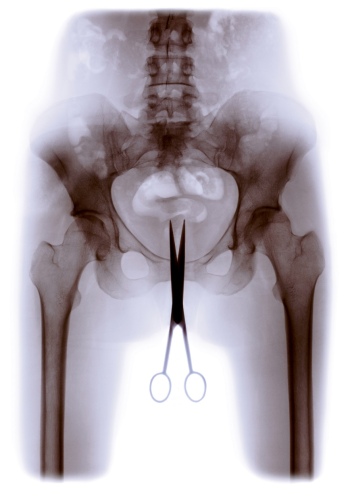

Die Ausstellung X-RAY zeigt u.a. das weite Spektrum der Röntgentechnik und ihrer Anwendungen von frühen Laboraufbauten und Röntgenbildern über das Pedoskop, mit dem man ab 1920 die passenden Schuhgrößen ermittelte, bis hin zu Röntgen-Satelliten wie eROSITA, die heute schwarze Löcher sowie Galaxien im Weltraum erforschen. Ob Nah- oder Fernsicht, im Zentrum steht immer die Durchleuchtung von unbelebter wie belebter Materie. Ikonisch wird der Röntgenblick im „Gläsernen Menschen“, entwickelt Ende der 1920er Jahre vom Deutschen Hygiene-Museum Dresden, der den komplexen Aufbau des menschlichen Körperinneren exemplarisch sichtbar werden lässt.

Die bildgebenden Verfahren der Röntgentechnik haben sich immer mehr verbessert (CT u.a.). Bei Untersuchungen wird die Strahlenbelastung heute so gering wie möglich gehalten. Während die Radiologie zur immer wieder weiterentwickelten Routine geworden ist, zeigen sich kulturelle Akteur:innen bis in die Gegenwart in unterschiedlichster Weise von diesem Phänomen fasziniert.

Die kreativen Mittel der weltweit aktiven Künstler:innen, die Werke durch Röntgenstrahlen, mit Röntgenbildern oder inspiriert vom Röntgenblick geschaffen haben, reichen vom Einsatz originaler Röntgenbilder, die zugeschnitten, übermalt, durch unterschiedliche Materialien und Farben bearbeitet, ergänzt und collagiert werden, über digitale Vergrößerungen, die als Vorlagen für Glasfenster verwendet werden, bis hin zu grafischen Simulationen des Phänomens. Radiologische Motive tauchen als Teilstücke in Gemälden, Skulpturen und Grafiken auf. Totenschädel als Vanitas-Motiv und Skelette setzen die lange Tradition des Memento Mori und Totentanzes auf ganz eigene Art fort.

Röntgenbilder zeichnen sich als Bildträger durch Verfremdung, schattenhaften Entzug der dreidimensionalen Räumlichkeit, metaphorisch durch das Sichtbarmachen des Unsichtbaren und verborgener Strukturen aus, also durch eine Abkehr von der traditionellen, realistisch-mimetischen Wiedergabe der Wirklichkeit. Auch deshalb wird dieses Medium, entwickelt an der Schwelle zum 20. Jahrhundert, zum Kennzeichen moderner Kunst.